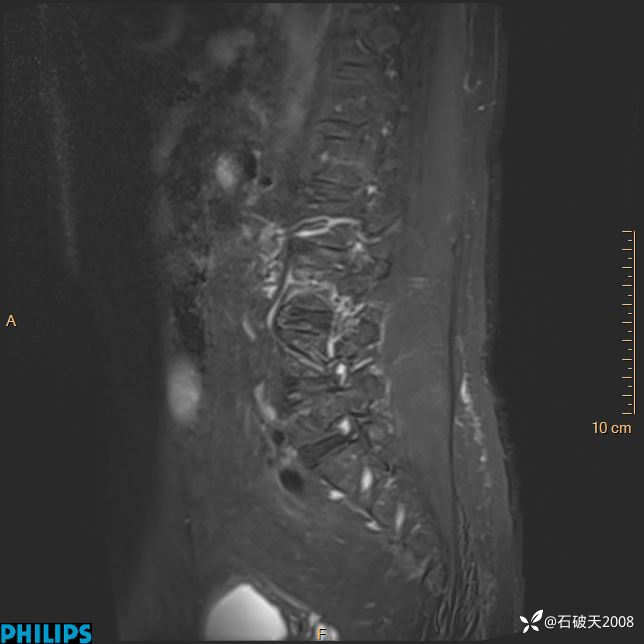

2023年3月份MRI影像

DWI